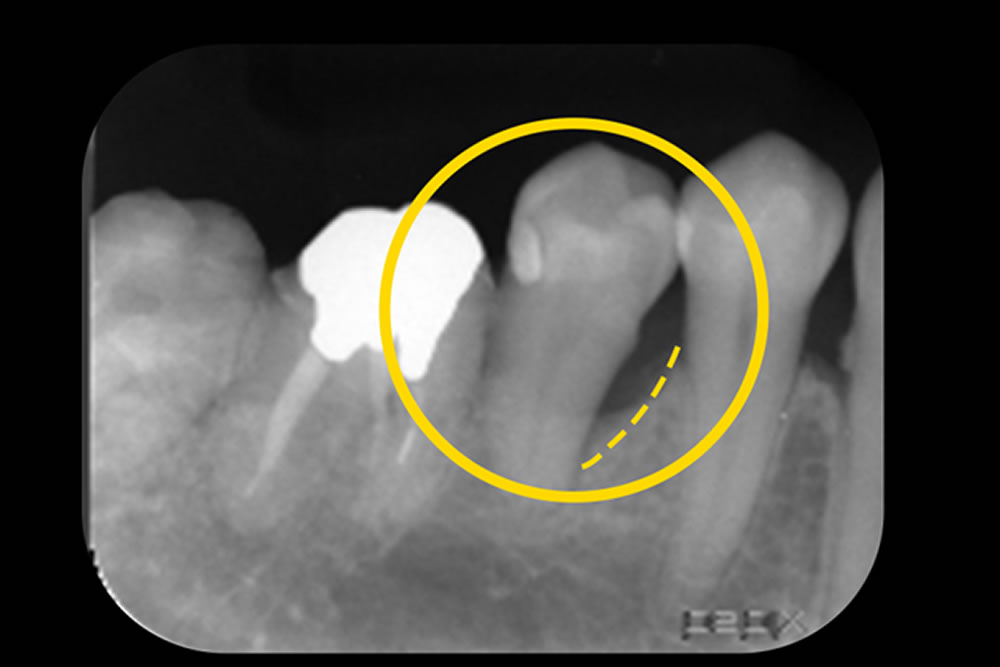

MINSTによる低侵襲な重度歯周病治療症例

| 主訴 | 歯がグラグラする |

| 治療内容 | ・低侵襲非外科治療(MINST)「歯茎を切らない歯周病治療」 ・レーザーペリオ治療 |